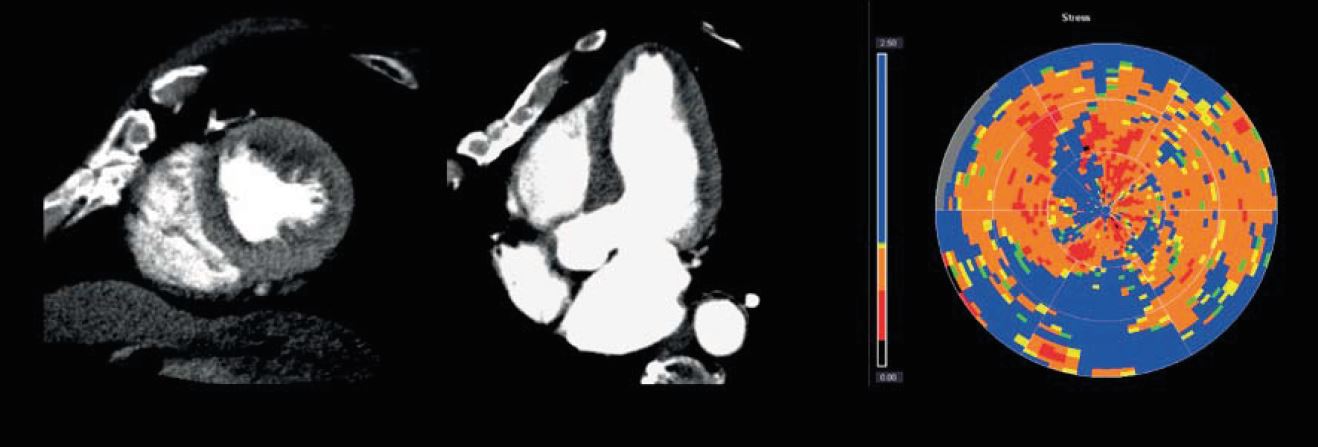

• Покращену діагностику, лікування та планування за допомогою гібридної візуалізації. Використовуючи технологію Smart Fusion, можна співвіднести ступінь коронарного стенозу на комп'ютерній томографіїз інформацією про розтягнення міокарда, отриманою за допомогою ультразвуку на навколишній міокардіальній території.

CT Myocardial Perfusion

Myocardial Perfusion Imaging

Точна ідентифікація уражень, що обмежують кровотік та потребують реваскуляризації, за допомогою візуалізації перфузії міокарда. Отримання об'ємного зображення всього серця за одне обертання при наднизькій дозі за допомогою                Aquilion ONE / GENESIS Edition.